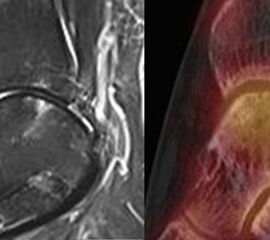

Abbildung 8.4.a bis d: Bilder einer Patientin mit chronischen Schmerzen im lateralen unteren Sprunggelenk links. Im MRT V. a. akzessorisches Knochenelement. Anamnestisch Beschwerden im Bereich des linken Sprunggelenkes seit 5 Monaten. Zuvor intensive sportliche Betätigung. Unter anderem tägliche atypische Belastung beider Füße durch Hinknien im Rahmen der Tätigkeit als Erzieherin. Diese Patientin hat nebenbefundlich bilaterale Akzessoria bzw. einen beiderseits angelegten Talus secundarius, der linksseitig jedoch nicht für die Symptomatik verantwortlich ist (die Bilder davon werden in Abbildung 3.5. gezeigt). Verantwortlich für die Symptomatik ist ein links posterolateral am Talus atypisches Knochenelement in einer Mulde mit engem Bezug zum unteren Sprunggelenk, DD atypisches laterales Os trigonum oder DD atypische Osteochondrosis dissecans. Die MRT konnte nicht differenzieren, wo die Schmerzursache genau lag. Im SPECT/CT (Abbildung 8.4.b und d) eindeutig fokale Mehrspeicherung im Bereich des atypischen Knochenelementes. Intraoperativ bestand der Aspekt einer Osteochondrosis dissecans.